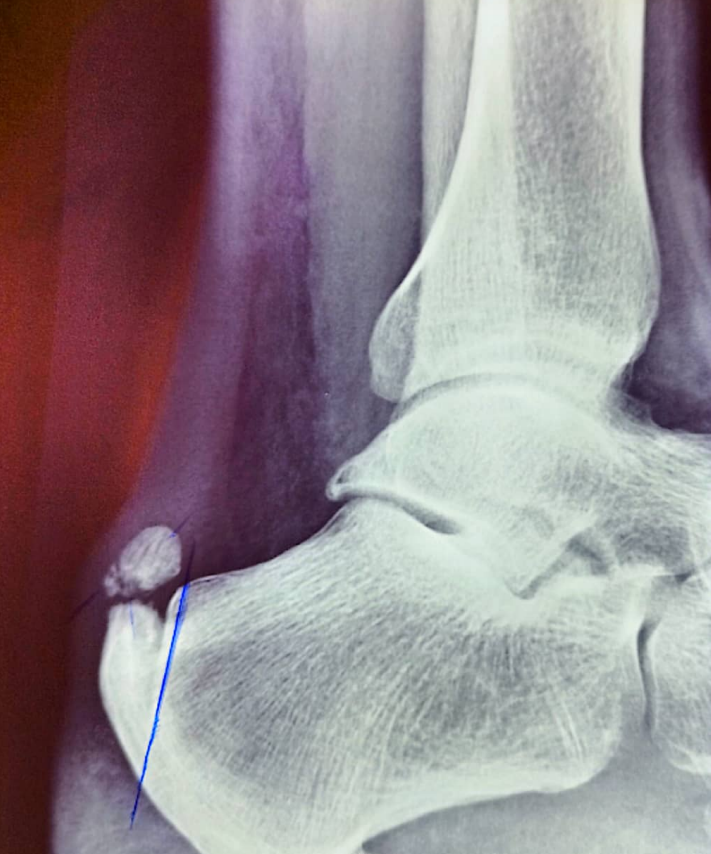

O diagnóstico é clínico é realizado pelo médico que apalpa o local e expõe o pé a carga durante a realização de testes, esses geralmente vão provocar dor específica no local.

Exames de imagem como Raio X , ultrassom e ressonância magnética mostram que além da calcificação ( espícula no local) , e inflamação local provocado pelo excesso de pressão por exemplo.